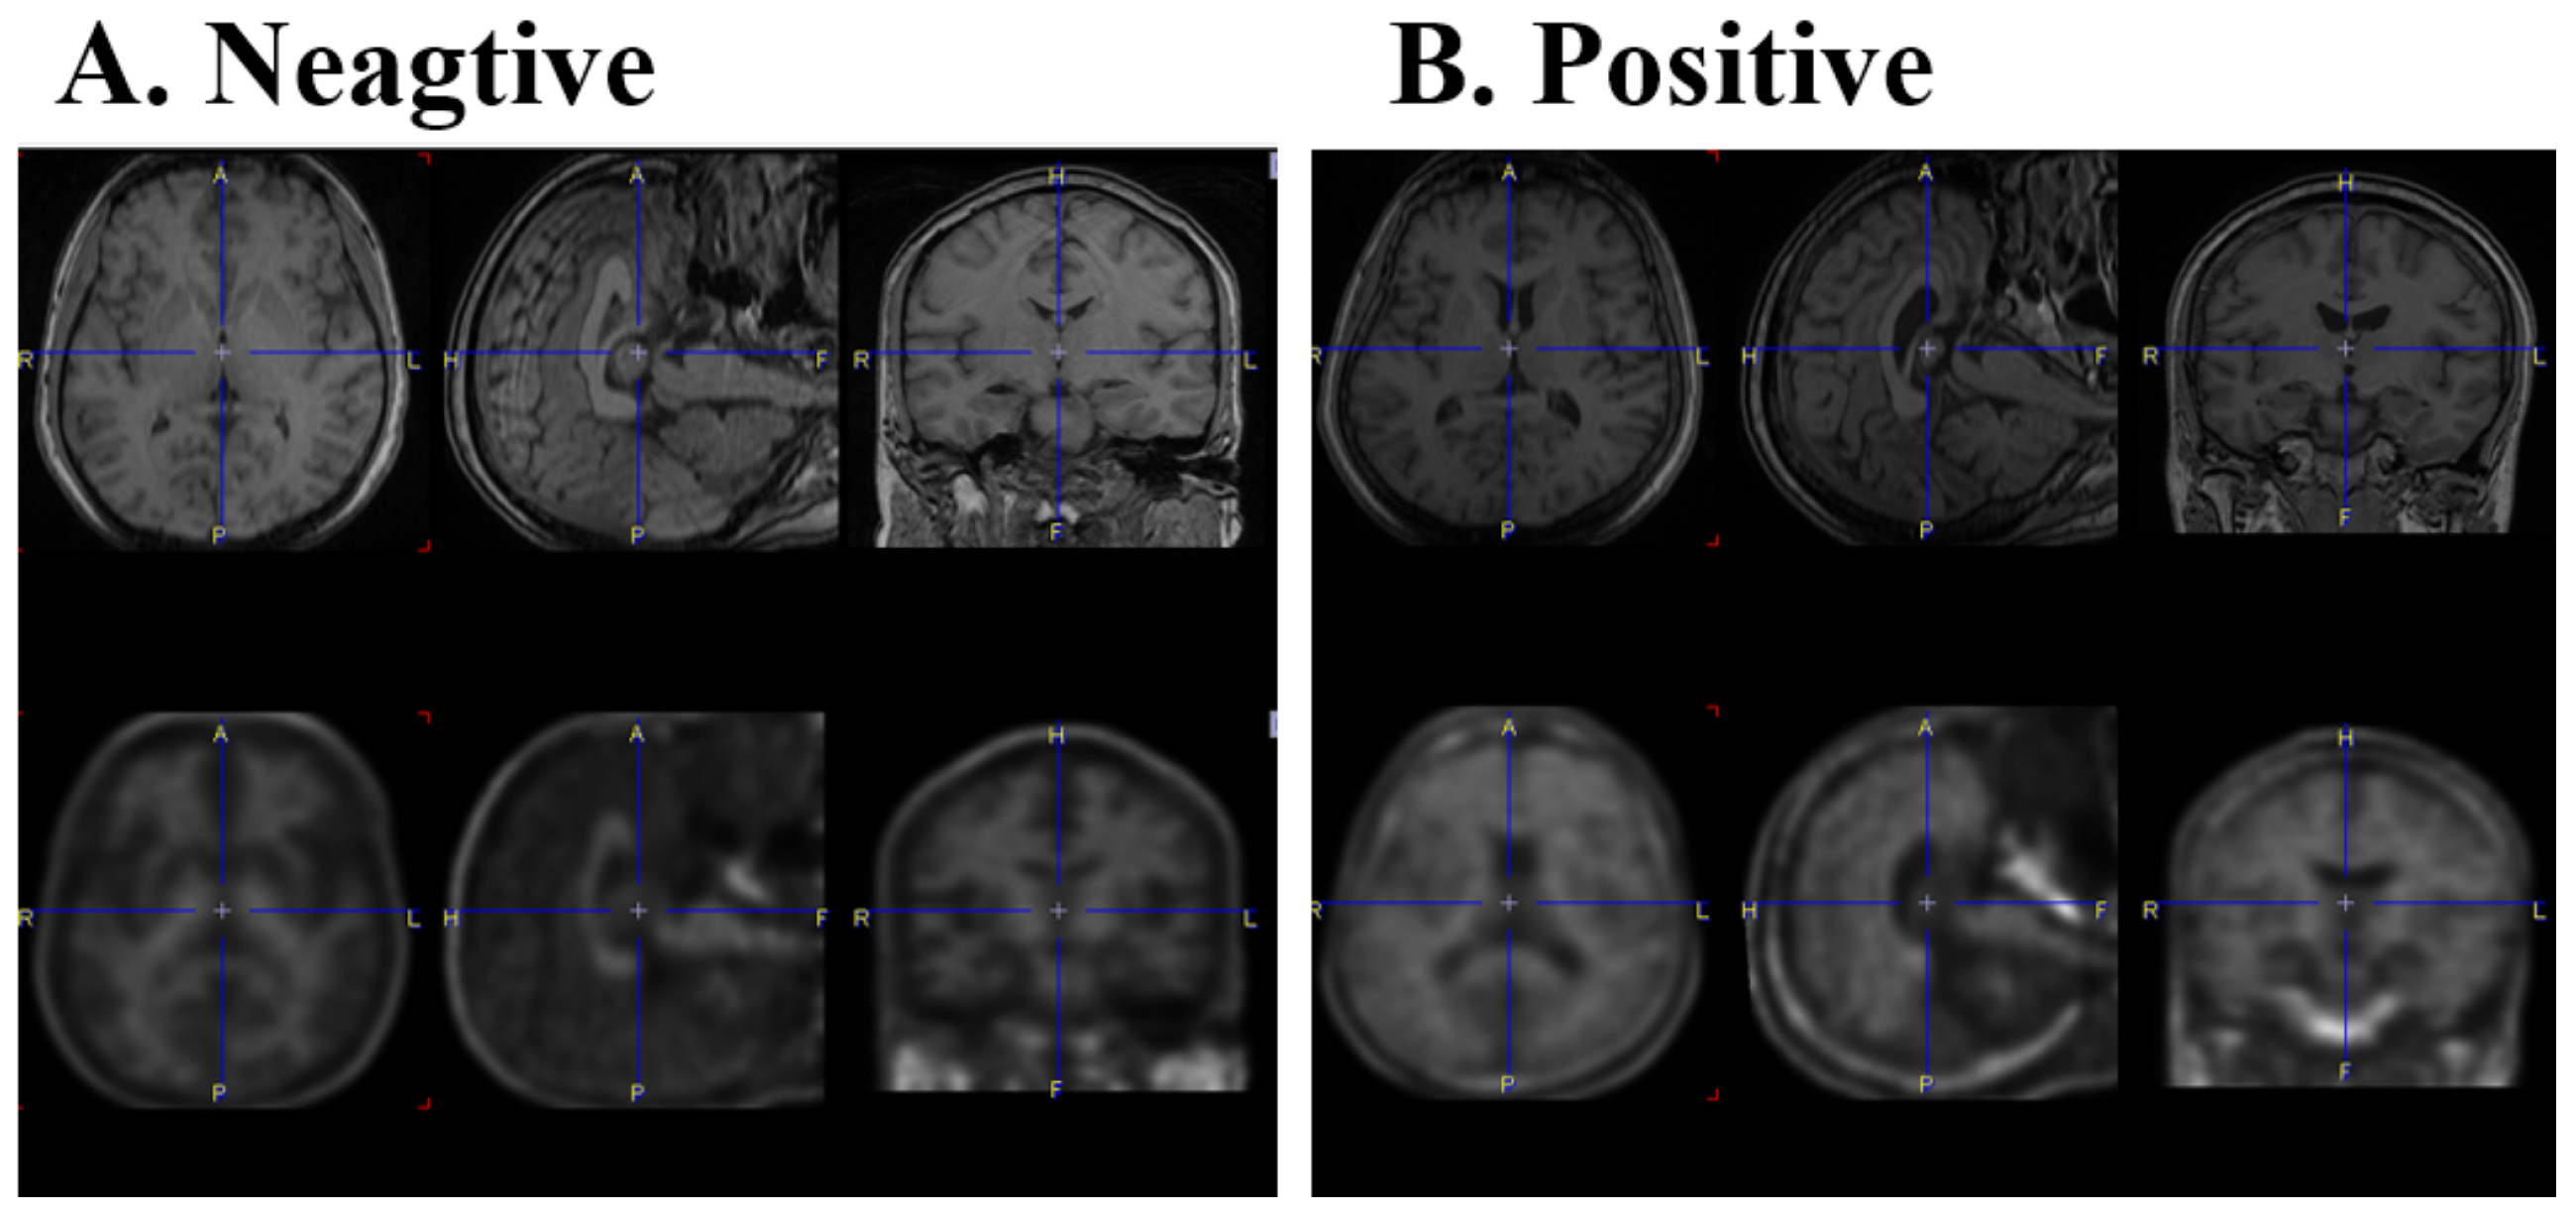

2.2. Image Scan

2.3. Images and Statistical Analysis